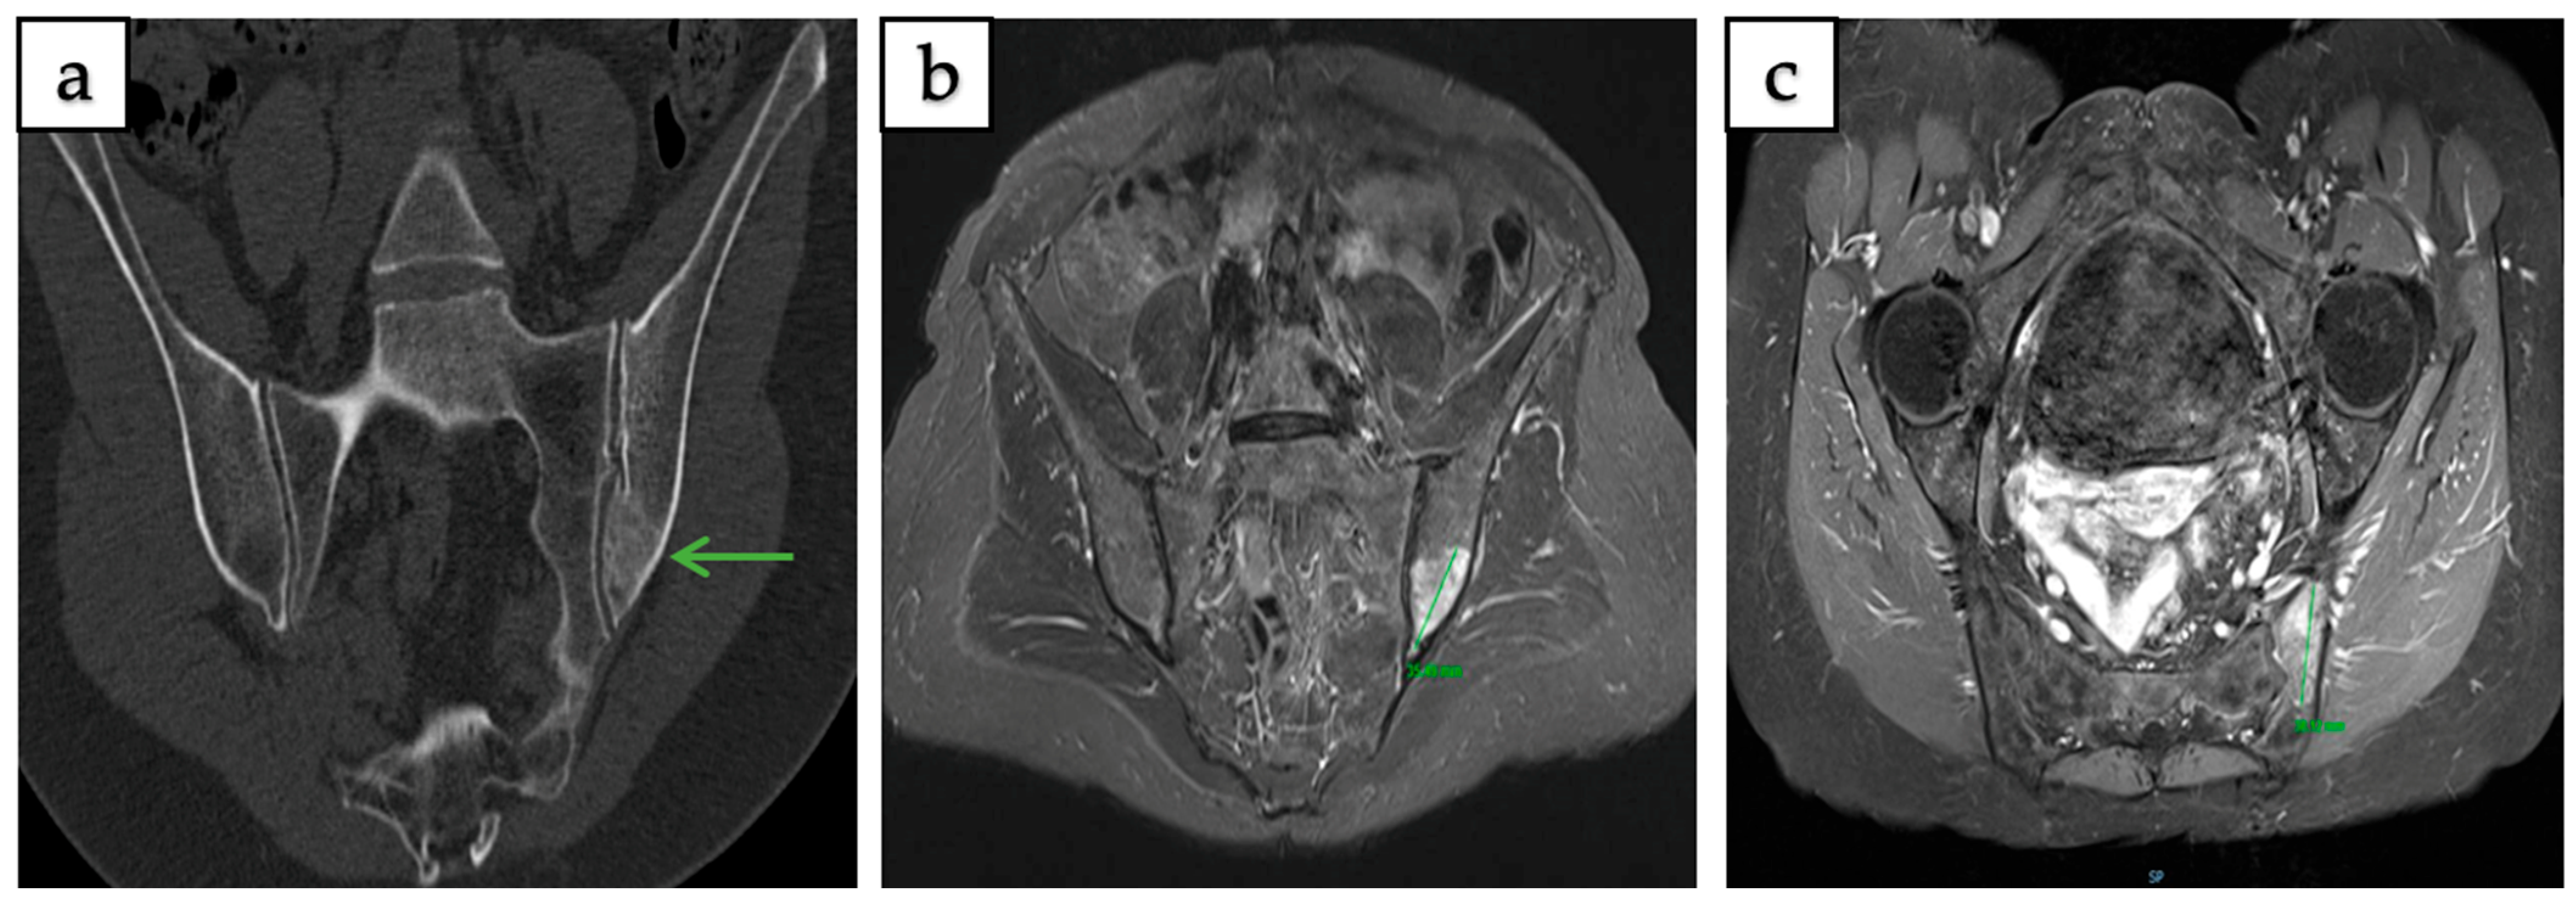

| Weiss et al., 2022 [12] | USA | Case Report | 2 | Right sacral wing, right sacral ala | Chronic right hip pain, chronic midline lumbar back pain | CT, MRI, 18F-FDG PET/CT |

| Myslicki et al., 2019 [13] | USA | Case Series | 5 | L2 vertebral body, right sacral ala, Right hemisacrum at S2, left posterior superior iliac spine, left proximal femur | Various (incidental findings, pelvic pain) | CT, MRI, Bone scintigraphy/SPECT |

| Kumar et al., 2011 [23] | USA | Case Report | 1 | Left sacral ala (pelvis) | Low back pain radiating to the left lower limb | CT, MRI |